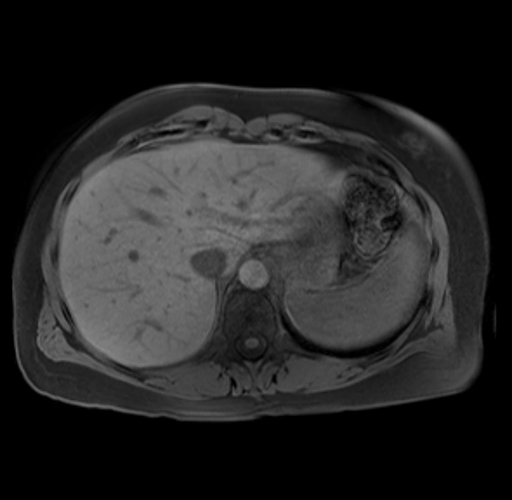

Imaging Analysis

Look through the patient's CT scan to identify any areas of concern for the necessary procedure.

Based on your CT findings, which issue(s) are present and would give reason for "planned slowing down moment(s)" in this case?